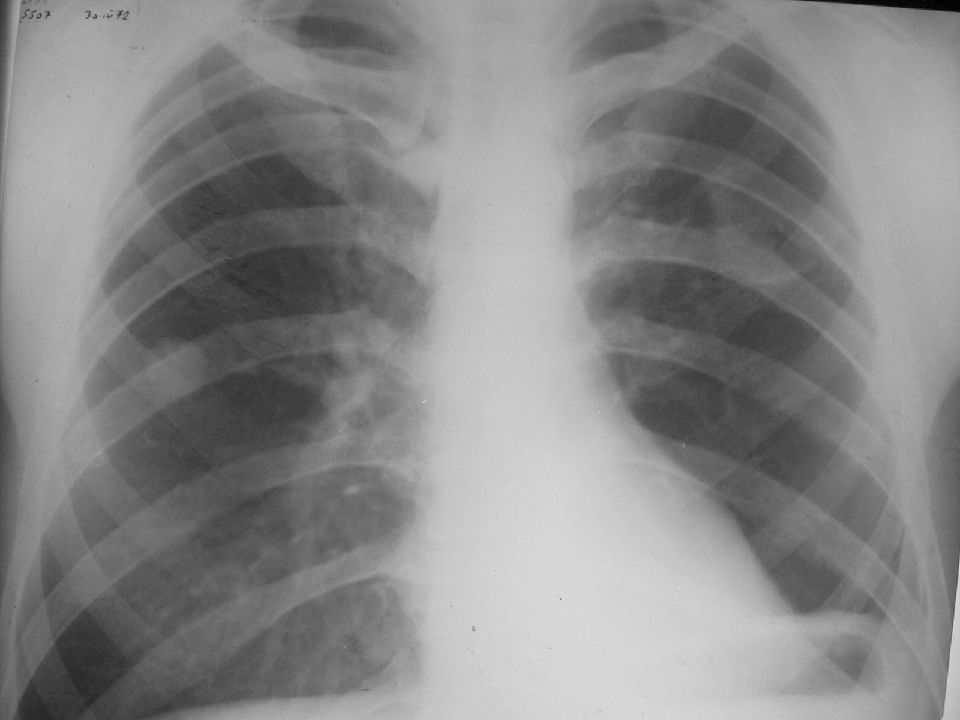

Рентгенологические изображения и синдромы патологии легких

Раздел: Кадры-подсказки